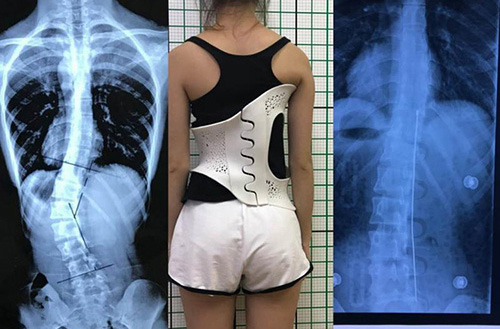

此外,在外固定支具研制方面,3D打印所起到的作用也不容忽視。對于意外摔傷導致骨折的患者來說,適宜的熱塑夾板、可卸式泡沫夾板、高分子夾板等外固定支具,有助于幫助患者快速恢復,并降低發生二次骨折的風險。

3D打印技術在骨科的實際應用有哪些?(圖4)

(3D掃描和3D打印技術輔助制造的個性化脊柱矯正支具)